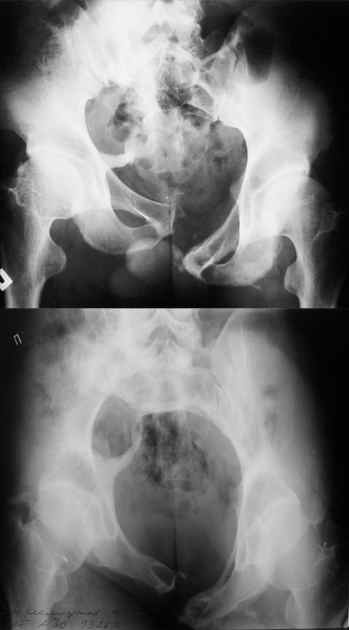

Re: Застарелое повреждение таза

Маленькая иллюстрация (около 5 лет после травмы). Результат плохой - укорочение, хромота, периодически боли в спине, но больной отказывается от операции, видимо, не так все трагично.